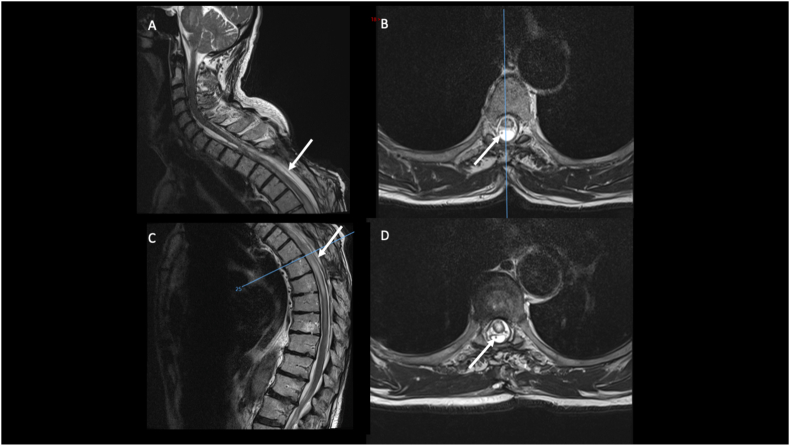

Figure 3.

Sagittal (A and C) and axial (B and D) views of T2-weighted MRI showing the postoperative results after the endoscopic opening of the cyst and the positioning of the cysto-peritoneal drain (arrow) under endoscopic-assistance. The patient experienced a neurological improvement and the follow-up images confirmed the reduction in size of the SAC with a relief of the mass effect on the spinal cord.